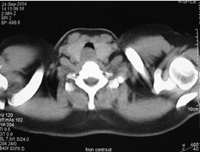

g/L。X线胸片示双肺野纹理稍厚。肺功能检查流速-容量环可见吸气平台(图1)

,符合胸廓外气道非固定性梗阻的特点。胸部和

颈部CT可见胸廓入口处气

管内占位,余未见明显异常(图2)。支气管镜发现在声门下约2 cm处有肿物,管腔大部分阻塞,支气管镜不能进入(图3)。患者转至外科进一步手术治疗。